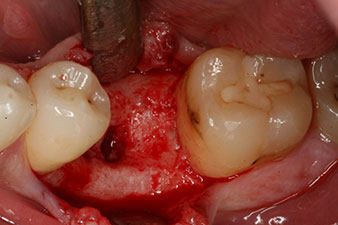

Implantat

Fig. 3: After preparation with the Implantmed implantology motor, an implant (diameter 4 mm, length 12 mm) was screwed in by the motor at a torque of 43 Ncm.

The implant was placed as planned after thorough removal of the granulation tissue (blueSky, bredent).

peri-implant bone deficit

Fig. 5: The peri-implant bone deficit must be compensated with autogenous bone chips to restore the peri-implant tissue contour.

These values could have indicated open healing or even immediate restoration. Due to the insufficient crestal bone volume at the implant, the region was augmented with the bone chips collected during preparation of the implant bed and sutured to exclude saliva.